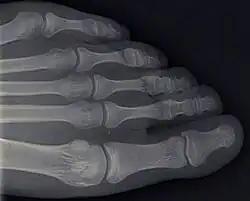

Die Zehenknochen (lat. Ossa digiti pedis oder Ossa digitorum pedis) sind die knöchernen Stützelemente der Zehen. Bei Säugetieren hat jeder vollausgebildete Finger drei knöcherne Stützelemente, die als Phalanx proximalis, media und distalis („körpernaher, mittlerer und körperferner Fingergliedknochen“), auch Phalanx I, II und III (von altgr. phalanx „Schlachtreihe von Kriegern“ „Baumstamm“, „Walze“, oder „Rolle“), bezeichnet werden. Die Großzehe besitzt nur zwei Phalangen, die mittlere ist nicht ausgebildet. Die Verbindungen zwischen Mittelfußknochen und Phalanx proximalis und den Zehengliedknochen untereinander sind die Zehengelenke.

Die Zehenknochen sind vom Aufbau typische Röhrenknochen und ähneln im Aufbau den Fingerknochen. Man unterscheidet von körpernah (proximal) nach körperfern (distal) Zehenknochenbasis (Basis phalangis), -körper (Corpus phalangis) und -kopf (Caput phalangis).

Die Zehenknochenbasis der Phalanx proximalis trägt eine konkave Gelenkfläche für das Zehengrundgelenk, die Gelenkflächen der Basis der unteren Zehengliedknochen einen sagittal gestellten Führungskamm. Die Gelenkflächen des Kopfes an Phalanx proximalis und media werden als Trochlea bezeichnet. Der Kopf des Endgliedes ist abgeflacht und trägt fußflächenseitig (plantar) eine Rauhigkeit, die Tuberositas phalangis distalis pedis.